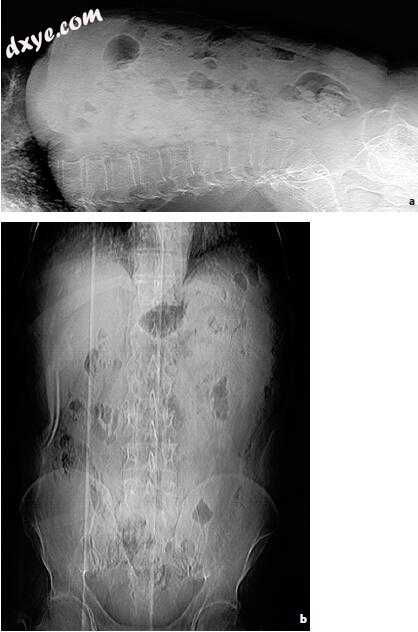

图5.8a-d。 反射性低渗性肠梗阻(RHI)的演变。 严重的心脏和循环衰竭。 腰椎(LL)仰卧位X线片。 气态小肠扩张。 b 24小时随访。 LL仰卧位X线片。 液体瘀滞的证据。 结肠受累增加腹部和肠道扩张。 RHI已变为麻痹性肠梗阻,伴有气液水平。 c,d后48小时随访。 (续.➝)

8-2.jpg

c LL仰卧位X线片。环直径和液体淤滞的进一步增加。音和运动减少达到完全麻痹。 d前后位仰卧位X线片。正面全景确认了小肠和大肠扩张。胃受累表明情况严重。减少音调和运动导致一些空肠环的水平分布。引入直肠导管以减少腹部和肠道扩张。患者在几小时内死亡